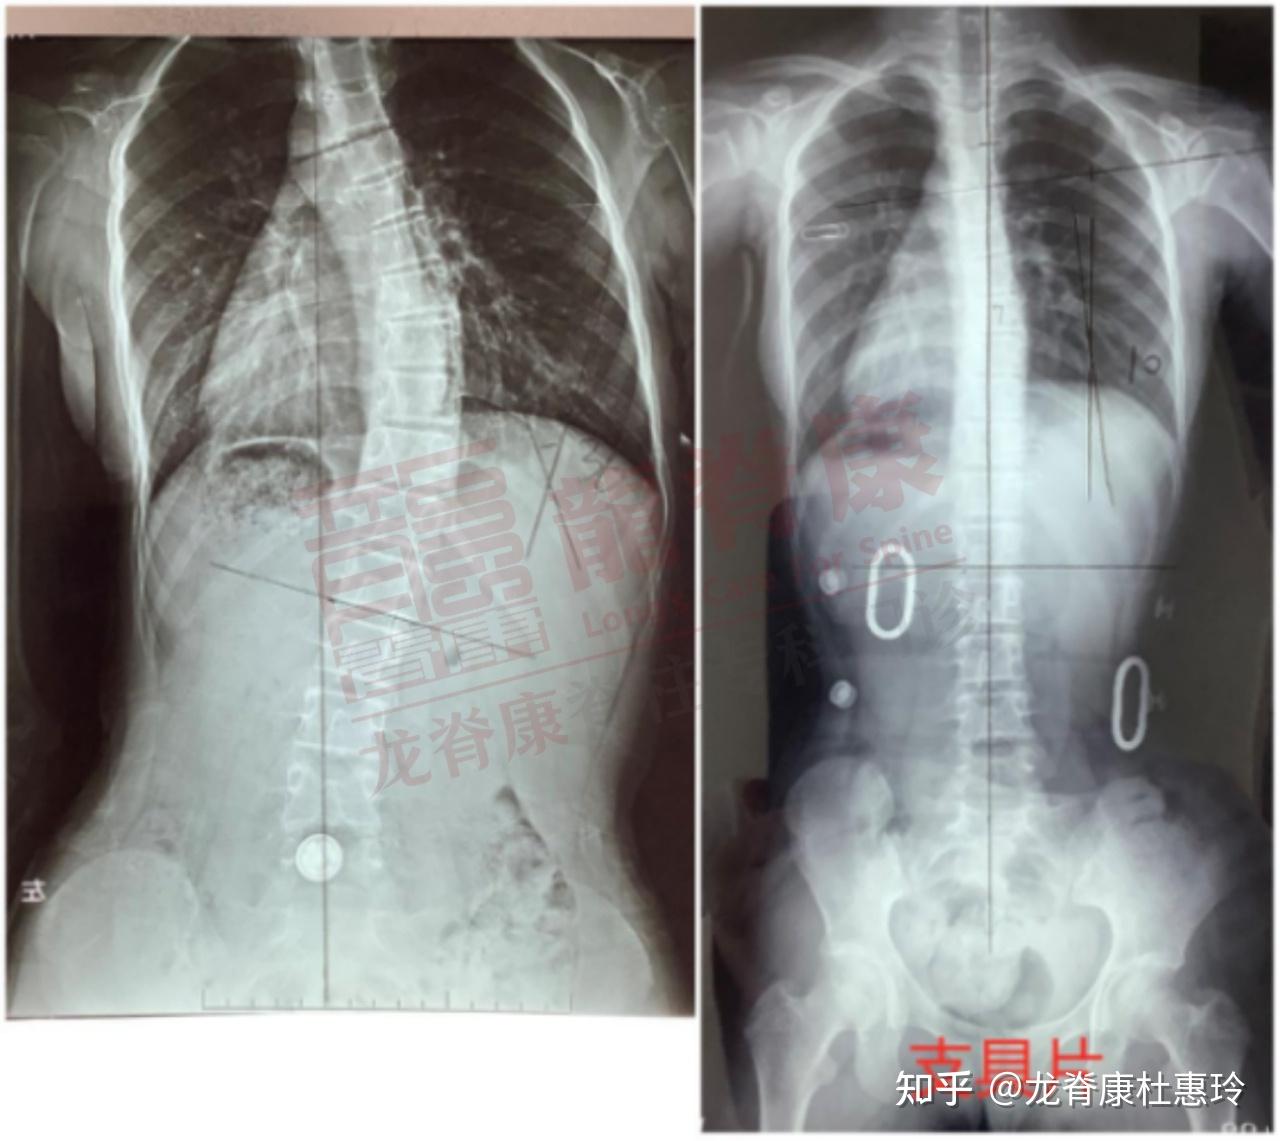

超过30度的脊柱侧弯怎么改善